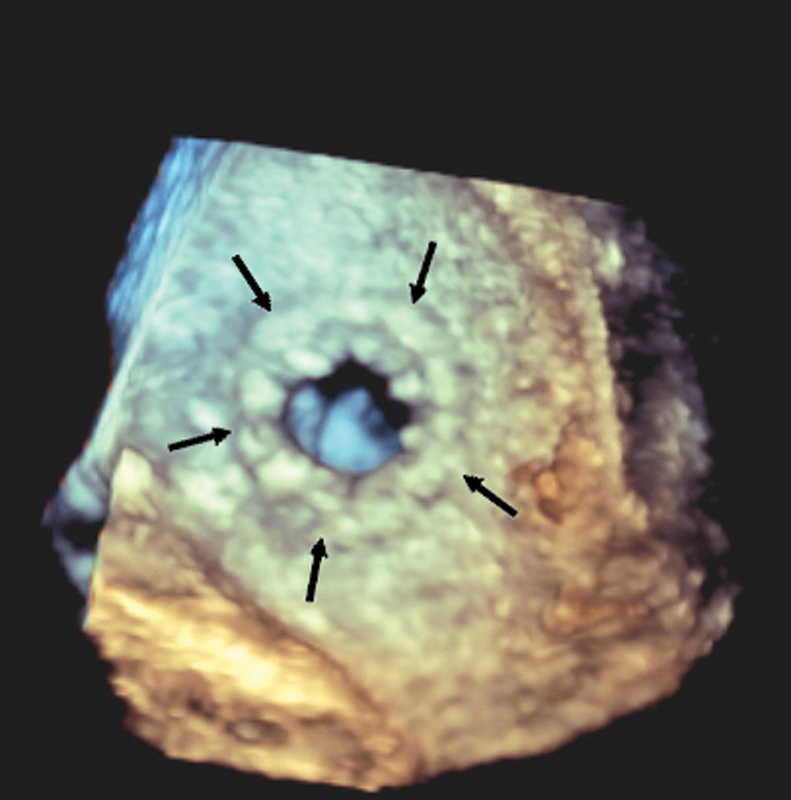

فحوصات تشخيصية لبعض امراض القلب والشرايين التاجية